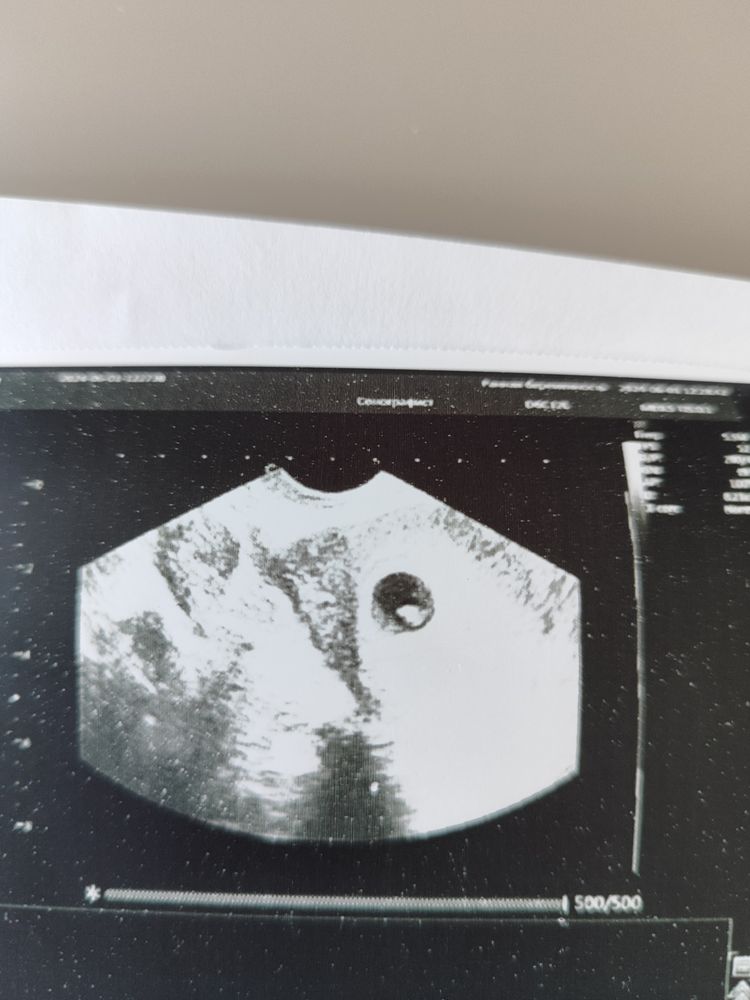

Подтвердилось, 5 недель 4 дня (7-8 акушерских)

Дождалась УЗИ, срок 5 недель 4 дня, в принципе всё, как я и рассчитывала) сердечко бьётся 😇

В понедельник пойду вставать на учёт, контроль УЗИ через три недели.

Можно поверить и тихонько радоваться ..